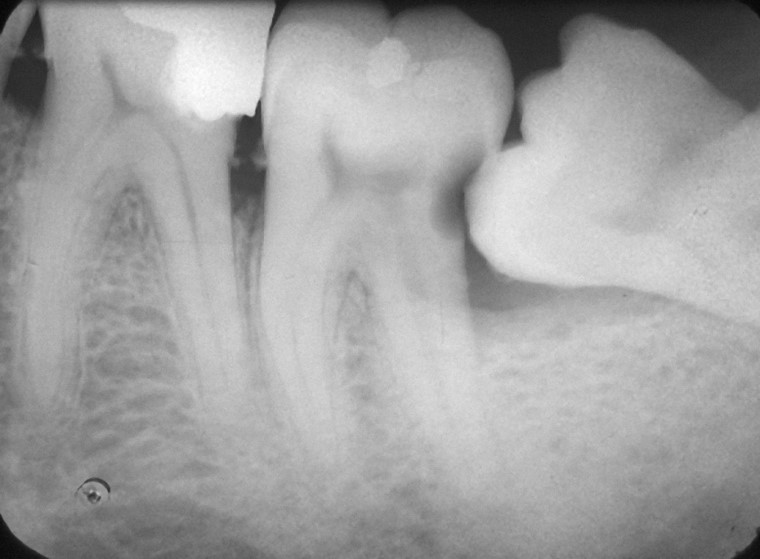

ΦΡΟΝΙΜΗΤΗΣ ΚΑΤΩ ΓΝΑΘΟΥ ΠΟΥ ΠΡΕΠΕΙ ΝΑ ΑΦΑΙΡΕΘΕΙ ΓΙΑΤΙ ΠΡΟΚΑΛΕΙ ΤΕΡΗΔΟΝΑ ΣΤΟ ΔΙΠΛΑΝΟ ΔΟΝΤΙ